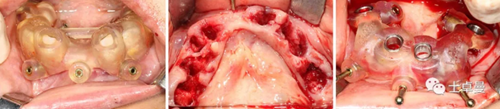

上頜種植手術

常規(guī)消毒碧藍麻局麻下,利用牙支持式導板確定固位釘位置后取下導板;

然后分離牙齦,于牙槽嵴頰腭側略翻瓣暴露牙根與牙槽骨間隙,切除齦瓣邊緣炎性肉芽組織,拔除上頜16-27牙,球鉆清理拔牙窩,并用大量生理鹽水沖洗;

通過先前固位釘位置安放固位釘支持式種植導板,因拔牙前后軟硬組織變化較大,需耐心尋找先前固位釘位置;

導板就位后利用Straumann BLT全程導板工具盒全程備洞,取下導板后利用測量桿確認種植體窩方向和深度以及種植窩周圍骨量;

植入6顆Straumann BLT種植體,植入扭矩均達到45Ncm以上:

16、26:4.1mm×14mm

14、24:4.1mm×12mm

12、22:3.3mm×12mm

安裝SRA基臺,均加力至35Ncm:

16、26:RC30°4mmA型

14,24:RC17°2.5mmA型

12,22:NC17°2.5mmA型

旋入SRA基臺保護帽,修整粘膜,縫合。